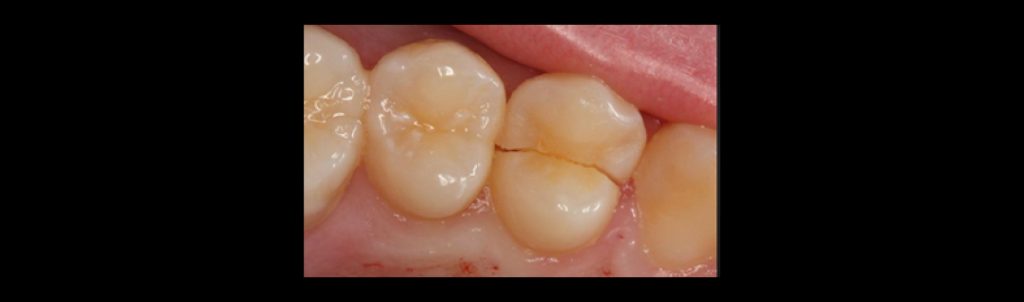

Cracked tooth

A cracked tooth has a fracture extending apically from the occlusal surface without complete separation of tooth structure and ends within the cervical area of the tooth. The involvement of one or both marginal ridges dramatically reduces tooth stiffness; specifically, losing one marginal ridge results in approximately a 40% loss of tooth stiffness, while losing both marginal ridges results in approximately a 60% loss of tooth stiffness.

These teeth often present with pain on release during biting. The pulp may or may not be vital. Cracked teeth are most often seen in restored teeth, but unrestored teeth can also fracture (e.g., a fractured cusp).

Treatment may include cuspal coverage, root canal therapy, or extraction. A 4–6-week provisional with cuspal support can help determine the long-term prognosis.